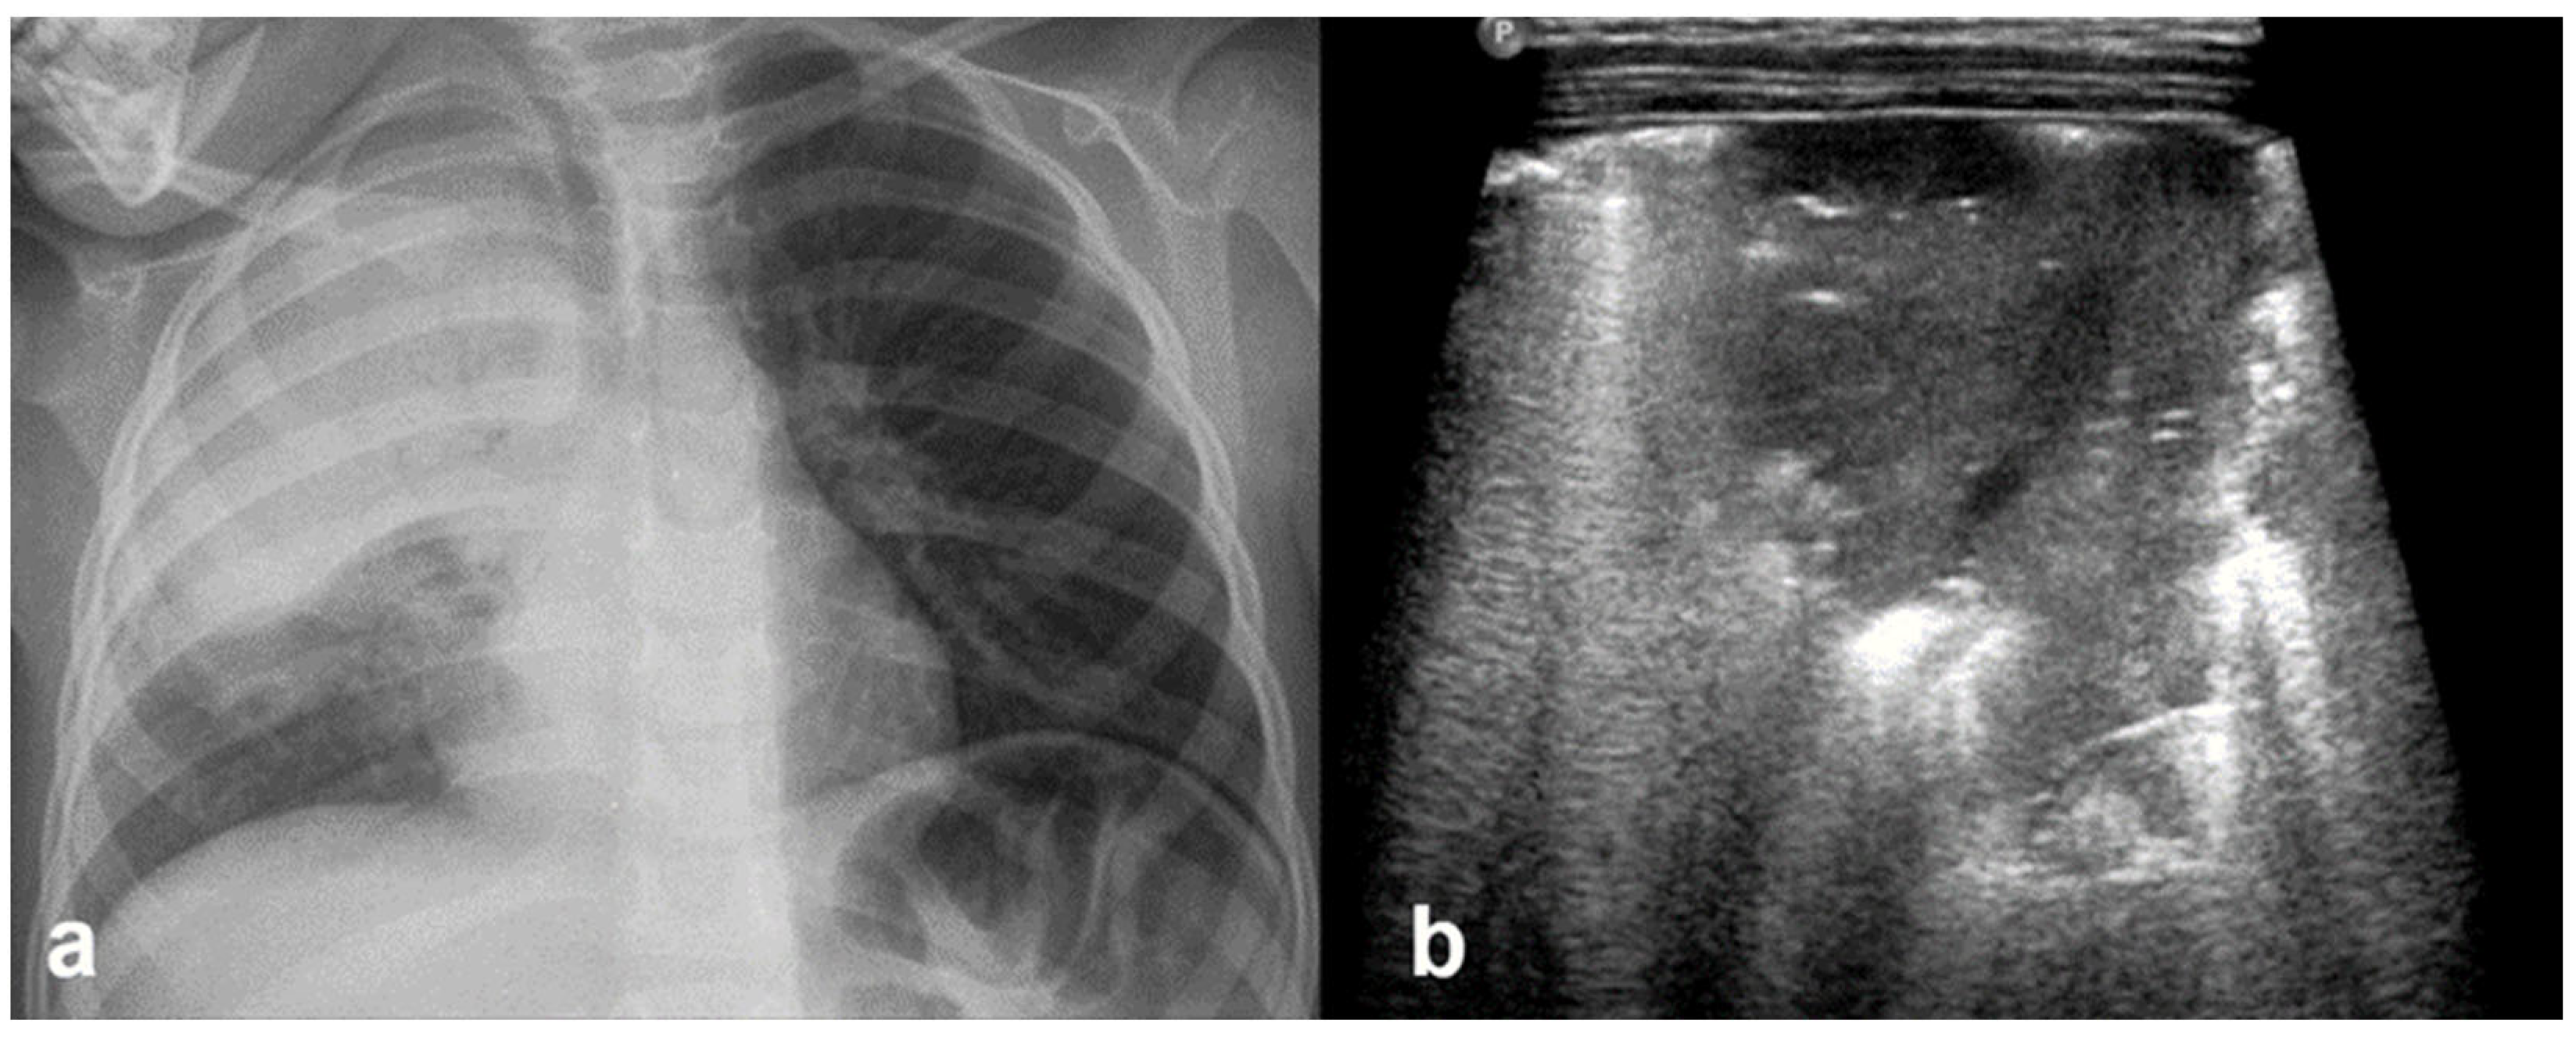

3.2.10. Pleural Effusion